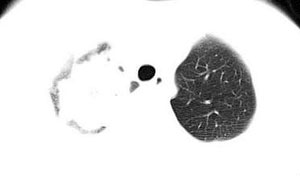

本病例特点如下:

1.青年女性,以胸痛20多天就诊,无呼吸道及感染临床症状体征,无原发肿瘤病史;

2.肺ct表现为两肺多发大小不等结节影,大结节位于肺尖部,小结节多位于肺外带胸膜下,大结节内可见支气管充气征,周围可见月晕征(指在结节状或肉芽肿样病灶周围呈环形磨玻璃影),右肺门及腔静脉后可见小淋巴结,右侧胸腔内少量液体。

考虑如下:

1.嗜酸性细胞肺浸润(好发于年轻女性,临床症状大多较清,类似loeffler综合征。影像呈非节段性均匀性肺实变,典型的有月晕征,分布于肺的外围,血常规嗜酸性粒细胞可增高,对激素治疗有效,临床症状和x线表现可迅速改善或消失),首先考虑本病。

2.结节病或wegener氏肉芽肿:前者可有多系统损害,多伴有纵隔或肺门淋巴结肿大;后者结节内有空洞是其特点。二者共同特点是好发于女性,x线表现重而临床症状相当较清。

3.霉菌感染:结合临床若有长期使用抗生素或激素类药物,患免疫力低下疾病可以考虑。

4.若有绒毛膜上皮癌和恶性葡萄胎病史,可以考虑肺转移,但影像表现不典型。